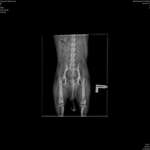

Unser Aussierüde wird diesen Monat 2 Jahre und irgendwie bin ich mir unsicher ob er Schmerzen in den Gelenken hat, oder nicht....unser Aussie ist noch nie gern gesprungen...,er braucht eine Weile um ins Auto zu hüpfen, er sitzt meist im schiefen Sitz , statt gerade und er hat auch sc ...